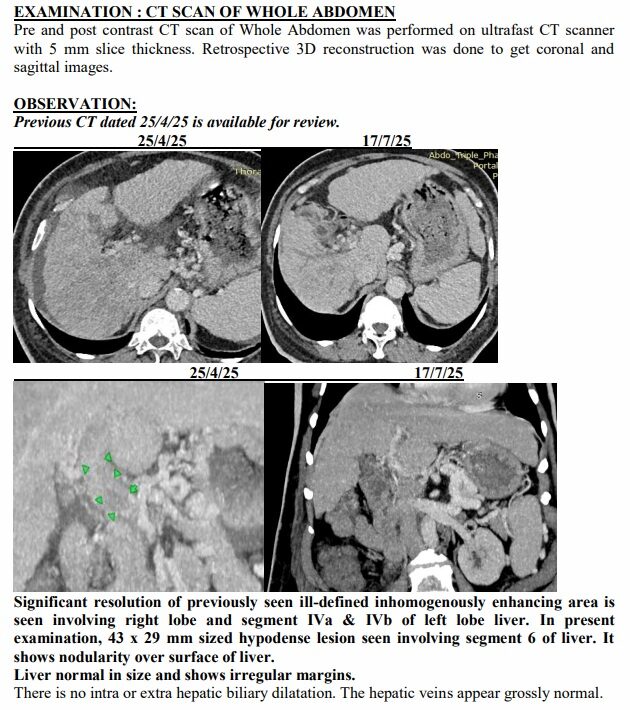

Yet just three months later, on another afternoon in July, the same family stared at a different scan. The tumours had shrunk to one patch. Blood was flowing again. The swelling was gone. Even the alarming tumour marker that had shot up to 1,000 ng/mL had fallen to 10, back in the safe zone. For a man who had been fading fast, it was a turnaround no one in the room dared to predict.

The July scan sealed what they were already feeling at home. The many shadows in his liver had shrunk into one. His abdomen, once swollen with fluid, was flat again. His numbers, which had scared even seasoned oncologists, were suddenly within range.